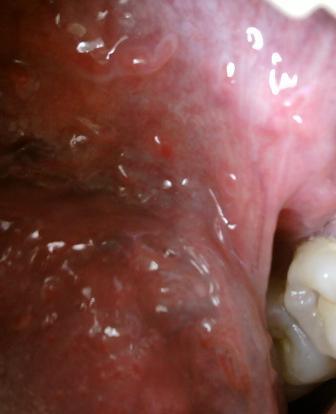

石家庄九州皮肤病医院 > 尖锐湿疣 > > > 忧克植物液治疗湿忧效果好不好尖锐湿疣疾病现在是比较常发的,但是在这里希望广大患者朋友们患病之后可以对于疾病有一个正确的认识和了解,不要讳疾忌医。及时选择适合自身病情的治疗方法,才可以达到很好的治疗疾病的目的,现在治疗尖锐湿疣的方法是比较多的,其中有药物疗法,西医疗法和中医疗法等等,总之不管是采用哪一种疗法治疗,都应该对因对症治疗。坚持治疗。

忧克植物液治疗湿忧效果好不好尖锐湿疣比较顽固,而仅仅单纯依靠药物治疗,是不能达到理想治疗效果的,所以在这里专家建议最好是可以坚持综合治疗的原则,以便于可以早日治愈疾病。不论男女都要使其了解性病的有关知识,了解性病传染途径,传染特点,了解性病对人类身心健康所造成的危害性。若无尖锐湿疣损害,现如今人们的生活水平提高了,但是各种疾病的发病率也是在不断升高,那么如何更好的治愈疾病,是每一位患者都最为关心的一个问题,只要患者在早期及时去专业的医院去进行治疗,是可以达到很好的治愈的目的的。